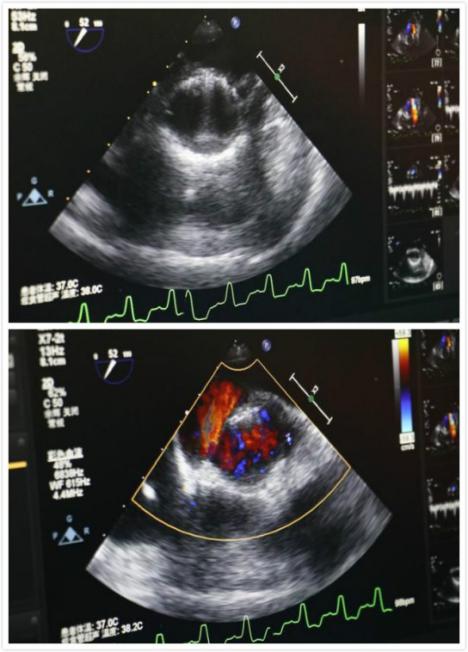

食道超声所示术中人工心脏

手术当日一早,手术相关科室通力协作,麻醉科、介入导管室进行了充分的麻醉及器械准备。11点手术正式开始, 全麻后,经左侧第五肋间小切口5cm依次经胸,显露心尖,双荷包缝合,穿刺心尖并置管,主动脉根部造影,显示:主动脉瓣重度关闭不全,根据术前CT和超声心动图测量的主动脉瓣环直径,选用29mm的J-Valve介入人工心脏瓣膜,植入原主动脉瓣环处。

再次造影及TEE显示:主动脉瓣无返流,介入瓣膜形态满意,无瓣周漏,无跨瓣压差。